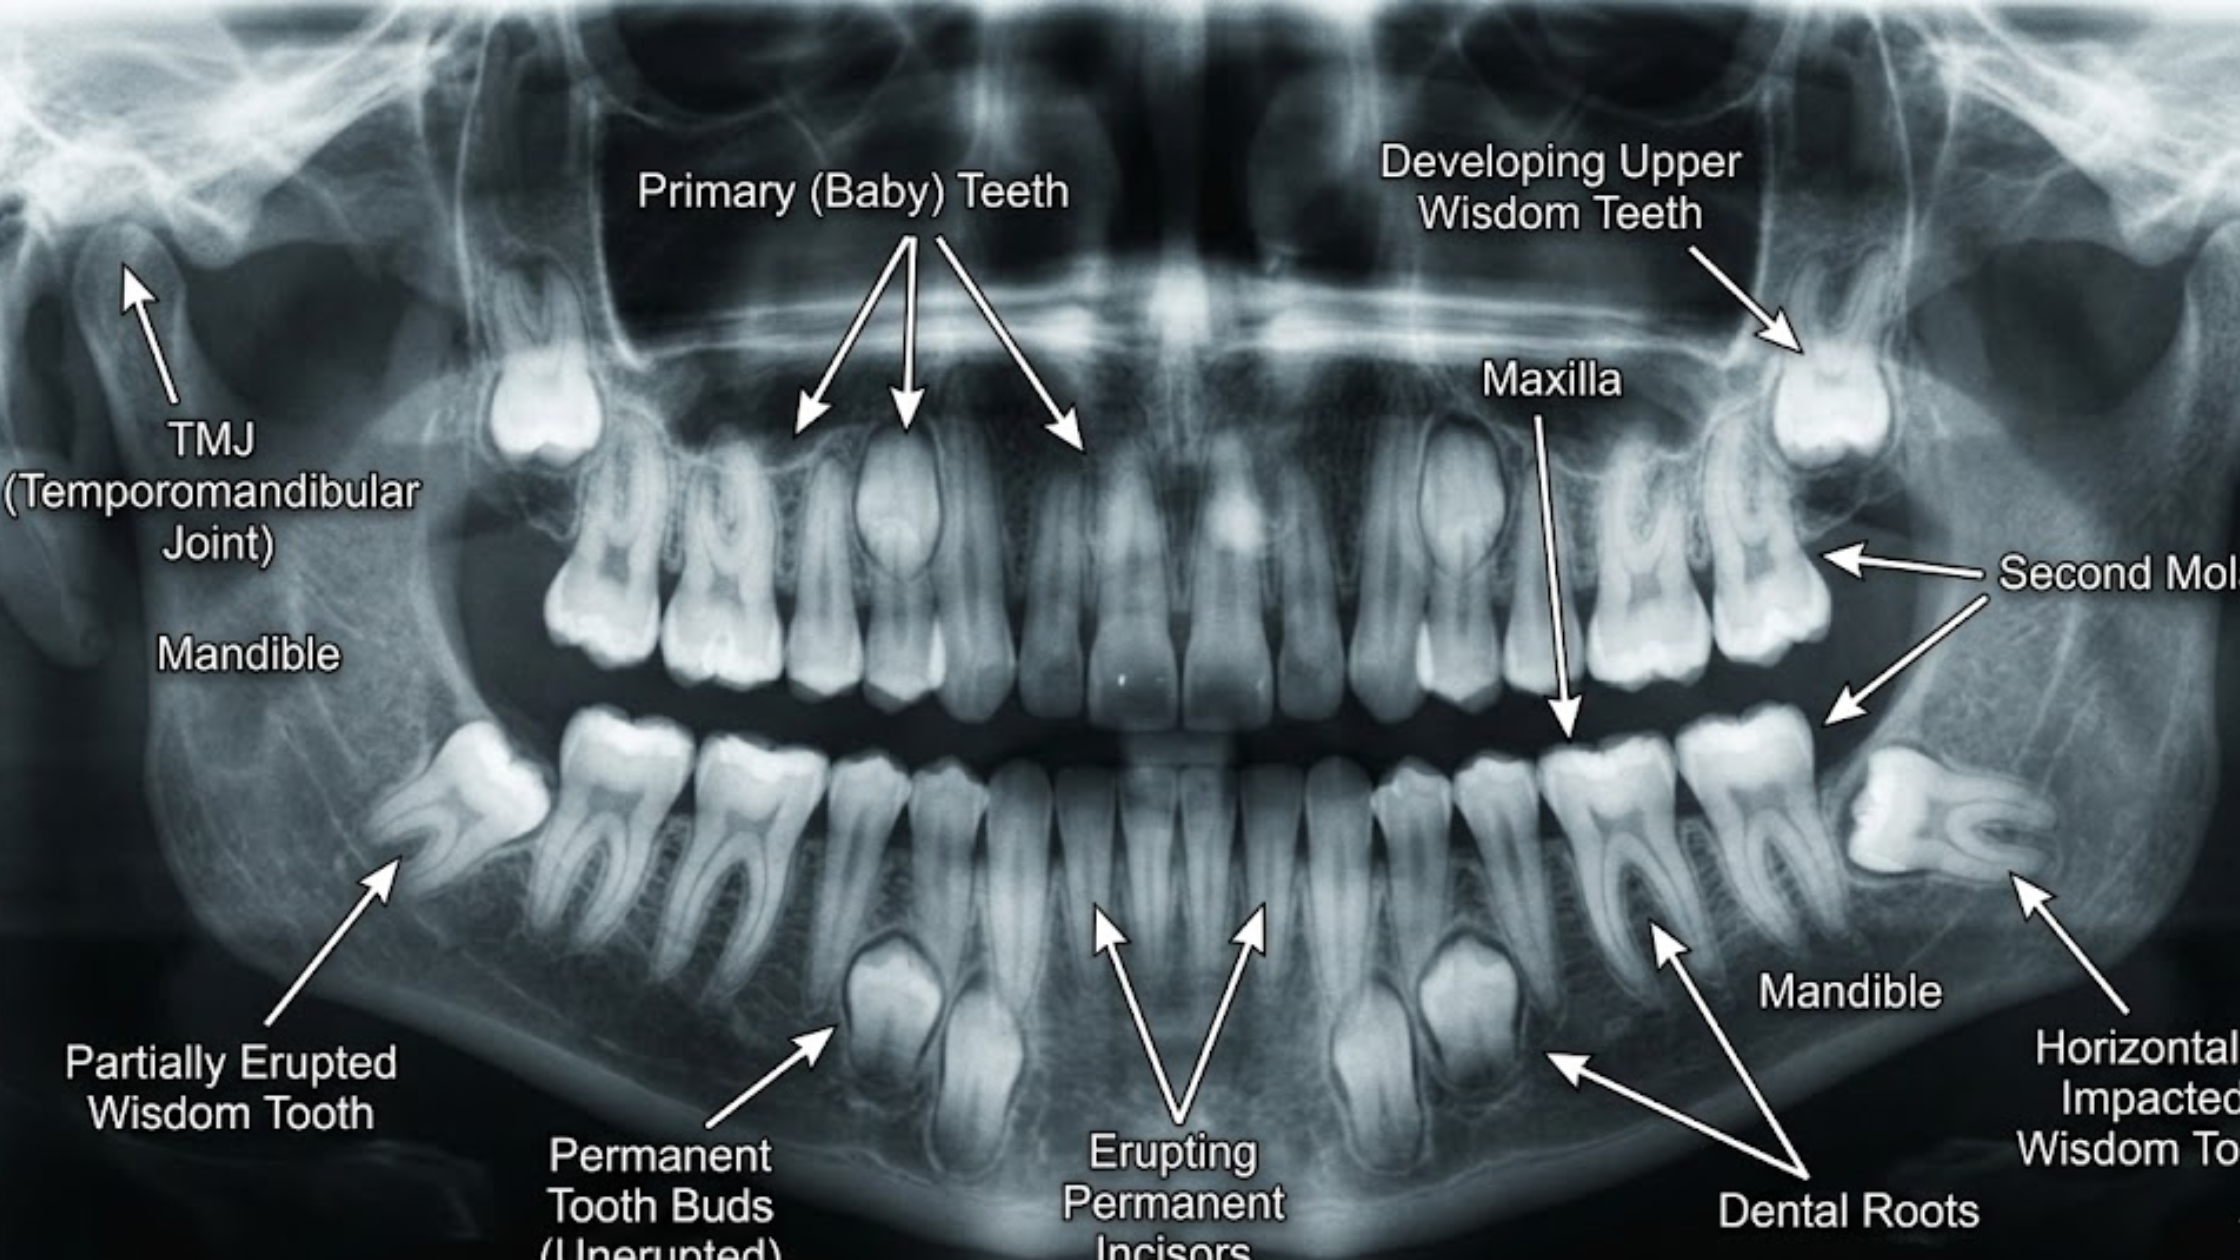

Developmental milestones are age-specific skills used to evaluate a child’s progress. These milestones and tooth eruption patterns assist caregivers and clinicians in monitoring dental development. A study was designed with these factors in mind.

Third molars, commonly called wisdom teeth, generally erupt between 17 and 21 years of age. Families should understand their potential implications, as these teeth can cause complications if not managed appropriately.

Wisdom teeth emerge in late adolescence or early adulthood. Common problems include:

- Impaction: Teeth may become trapped in the jawbone or gums, causing pain and infection.

- Crowding: They can push against adjacent teeth and affect alignment.

- Cysts: In some cases, cysts can form around impacted wisdom teeth, creating further issues.

The incidence of impacted third molars is substantial, with approximately 72% of Swedish individuals aged 20 to 30 years having at least one impacted wisdom tooth. Impaction results from limited space, obstruction, or abnormal position. Impacted teeth can cause inflammatory disease, manifested by pain and swelling, and may damage adjacent teeth and bone.